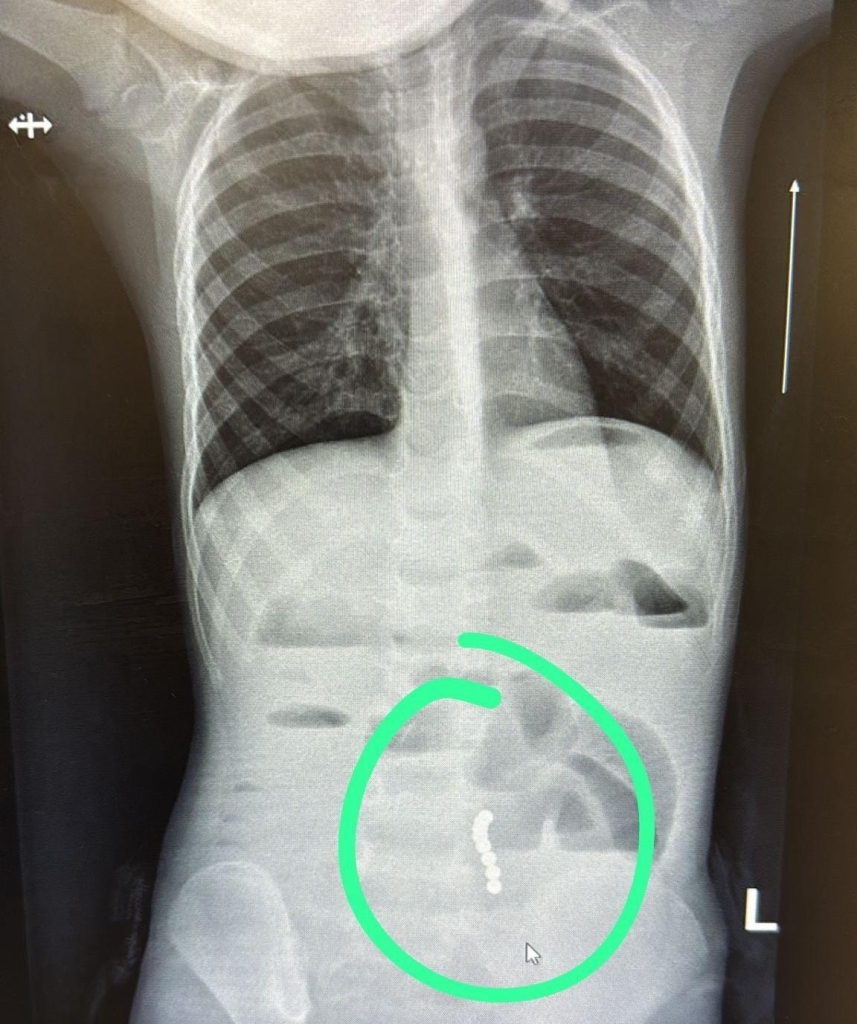

ד”ר ליאת יניב, רופאה בכירה במחלקת ילדים במרכז הרפואי בני ציון, זיהתה כי מדובר בהקאות ללא שלשולים ובעלות צבע חריג, ממצא שעורר חשד לבעיה משמעותית במערכת העיכול. בצילום הדמיה שבוצע בדחיפות, הודגמו מגנטים במעי הדק עם עדות לחסימת מעי.

בהתייעצות עם ד"ר ראוף נאסר, מומחה גסטרו ילדים, הפעוט הופנה להמשך טיפול כירורגי ונותח באופן דחוף ע"י ד”ר דניאל דובין, סגן מנהלת מחלקת כירורגיית ילדים במרכז הרפואי בני ציון ו ד"ר יאיר בן שמואל, רופא בכיר בכירורגיית ילדים, כאשר ד"ר אבו ראס עומר היה הרופא המרדים הבכיר. בניתוח הוצאו שמונה כדורי מגנט מהמעי הדק.

צילום: ד"ר דניאל דובין